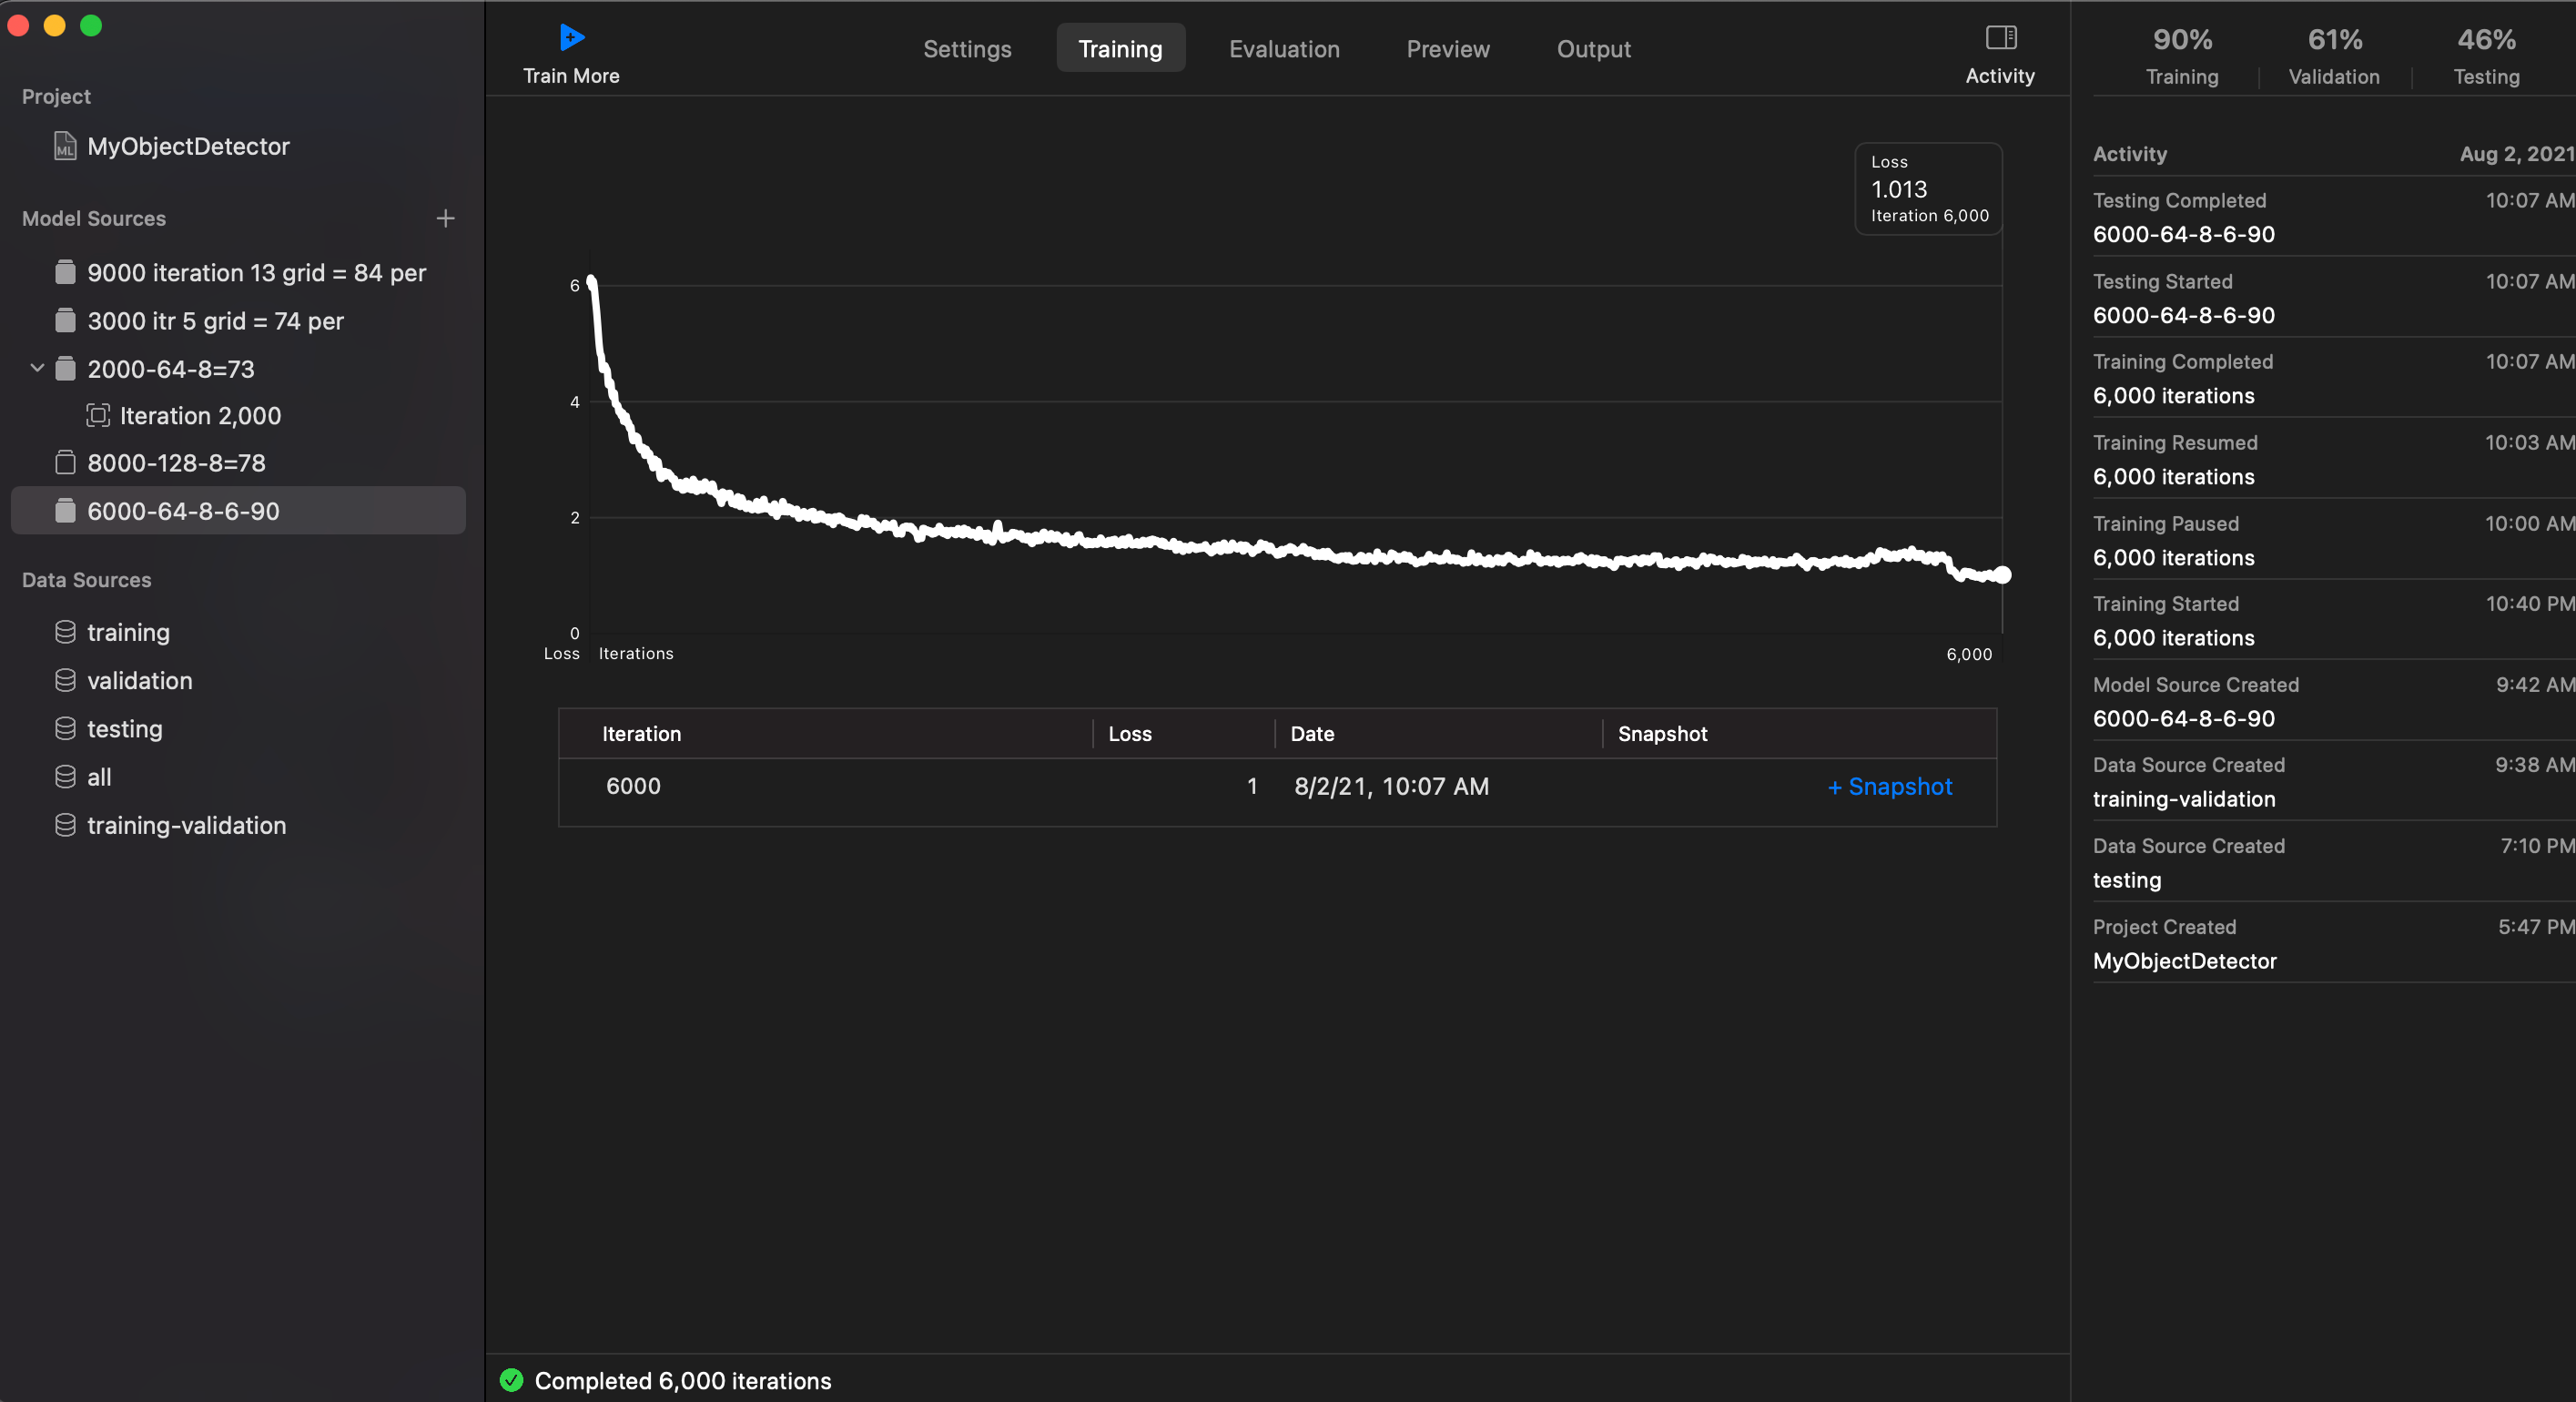

- Iteration: 6000

- Grid Size: 8 x 6 or could be 8 x 8

- Training and Valiation set: 850

- Testing set: 150

- Batch Size: 64

Loss: 1.013

Training: 90%

Training: 71%

Training: 46%